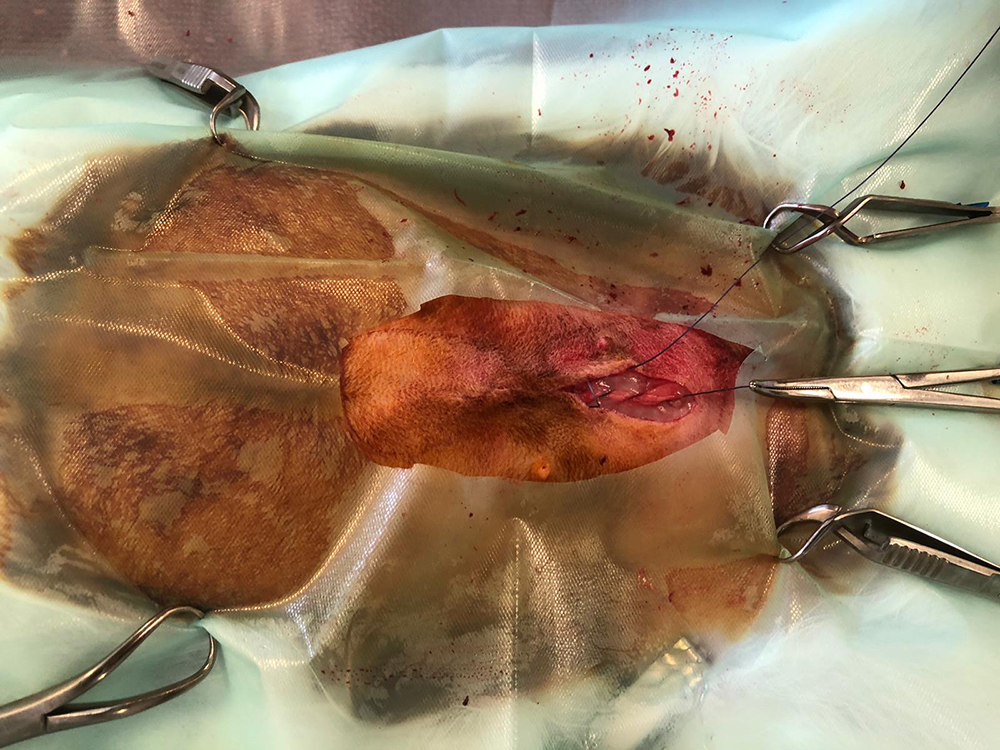

Hierna worden de buikwand, de onderhuid en de huid gesloten. Vaak is het weefsel heel dun waardoor het hechten lastig kan zijn. Het is zaak om de hechtingen goed onder de huid te krijgen.

Omdat een konijn zijn nachtontlasting moet kunnen opeten voor de bacteriën, is een kraag niet aan te raden. Soms zetten we aan de buitenkant van de huid nog een aantal steunhechtingen voor extra veiligheid.

Hieronder de sterilisatie van het konijn in beeld